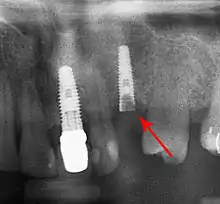

Long-term failures are due to either loss of bone around the tooth and/or gingiva due to peri-implantitis or a mechanical failure of the implant. Because there is no dental enamel on an implant, it does not fail due to cavities like natural teeth. While large-scale, long-term studies are scarce, several systematic reviews estimate the long-term (five to ten years) survival of dental implants at 93–98 percent depending on their clinical use.[1][2][3] During initial development of implant retained teeth, all crowns were attached to the teeth with screws, but more recent advancements have allowed placement of crowns on the abutments with dental cement (akin to placing a crown on a tooth). This has created the potential for cement, that escapes from under the crown during cementation to get caught in the gingiva and create a peri-implantitis (see picture below). While the complication can occur, there does not appear to be any additional peri-implantitis in cement-retained crowns compared to screw-retained crowns overall.[67] In compound implants (two stage implants), between the actual implant and the superstructure (abutment) are gaps and cavities into which bacteria can penetrate from the oral cavity. Later these bacteria will return into the adjacent tissue and can cause periimplantitis.